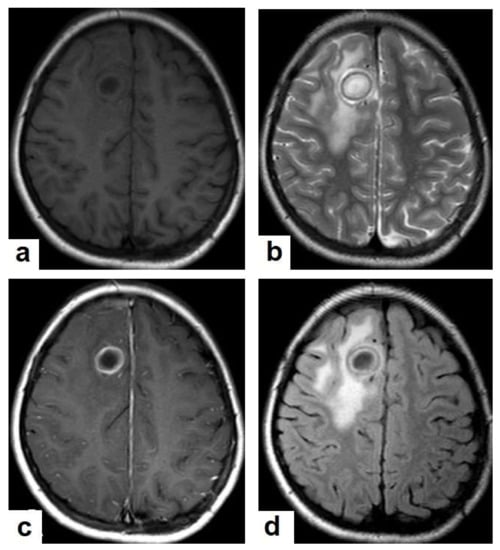

Figure 16. Tuberculous abscess in the right cerebrum of a 13-year-old female. Selected images of brain MRI (a) T1-weighted image (WI), (b) T2-WIs, (c) T1-WI with contrast, and (d) FLAIR-WI. The images show a well-defined lesion in the right cerebral hemisphere with low-signal-intensity content and a high-signal-intensity capsule on T1WI, which appear as high-signal-intensity content and a low-signal-intensity capsule on T2WI (b); there is marginal enhancement on T1WI with contrast administration (c), and there are low-signal-intensity contents and a high-signal-intensity capsule on FLAIR (d). Obvious grade-2 vasogenic oedema around the lesion on T2WI and FLAIR.

• Tuberculous abscesses (Figure 15, Figure 16 and Figure 17) are an infrequent pattern of brain TB, which are present in immunocompromised and elderly patients. They occur either due to the progression of cerebritis or the liquefaction of tuberculoma. On a brain CT, it occurs as a low density area with ring enhancement after contrast administration and the surrounding low density area of edema. On a brain MRI, it appears as a circular or elliptical area of low intensity with ring enhancement after contrast administration and surrounding low intensity area of edema on T1WIs and high intensity area with a high intensity surrounding edema. Tuberculous abscess is a difficult differential diagnosis of a pyogenic abscess, pilocystic astrocytoma, and other cystic lesions. MR spectroscopy may help in differentiating tuberculous from a pyogenic abscess [27,33].